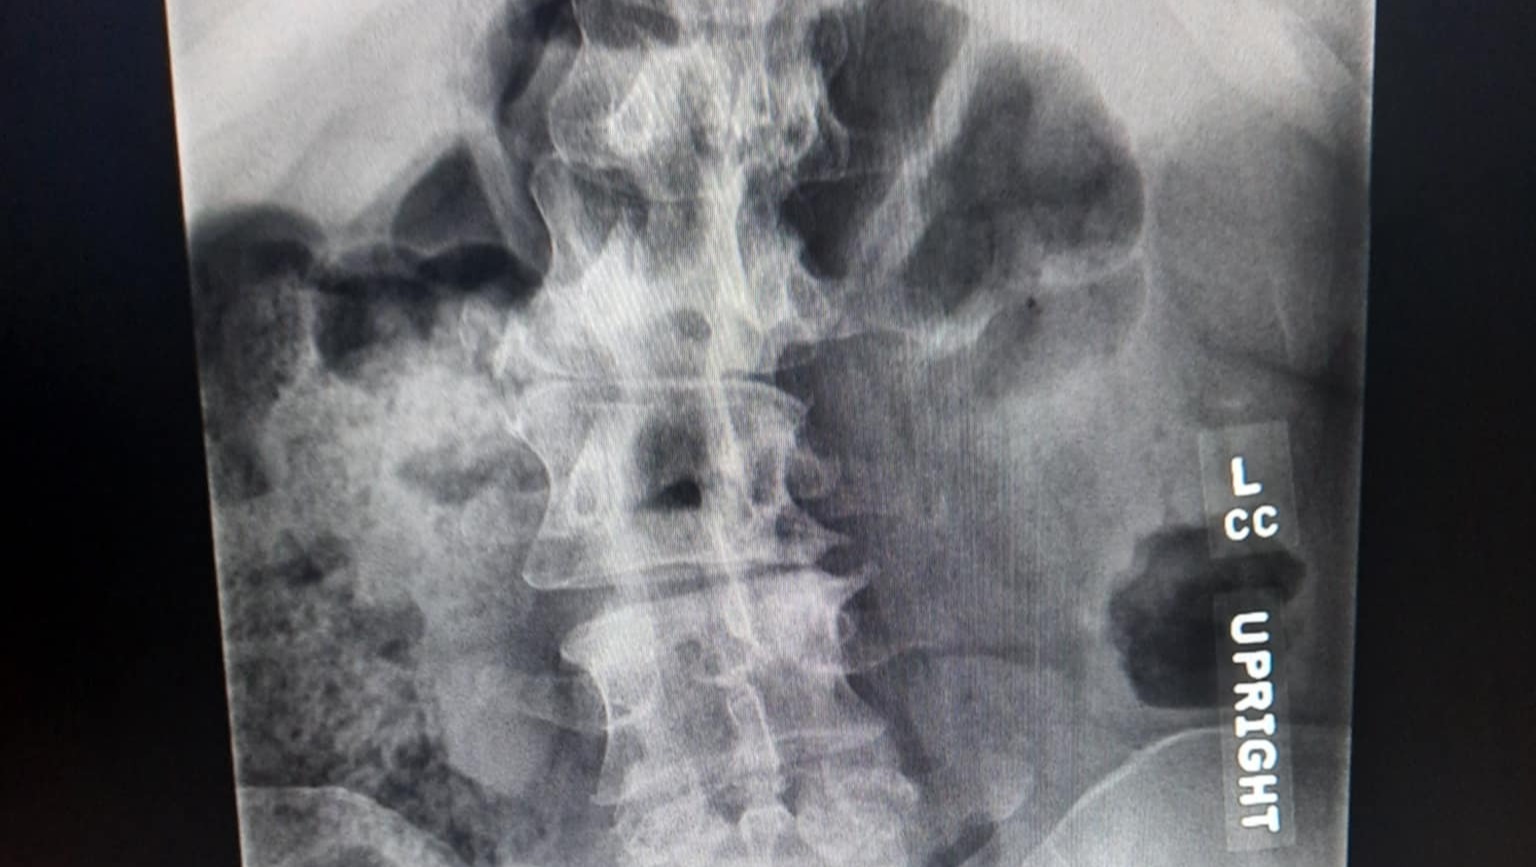

2/3/2026-XRay findings from 2/2/2026 Xray:

Findings/impression:

1. Right convex lumbar spinal curvature measuring 22 degrees.

2. Chronic L5 spondylolysis with stable mild anterolisthesis at L5-S1 which remains fixed between flexion and extension.

3. Mild fixed retrolisthesis at L3-L4 and L4-L5.

4. Stable multilevel disc degeneration, moderate in degree at L5-S1, and at least moderate multilevel facet hypertrophy.

Narrative

L SPINE W FLEX/EXTEND

Clinical Indication: Lumbar radiculopathy.

Comparison: External lumbar radiograph series 9/9/2025 and MRI 9/3/2025.

***New findings: "Mild fixed retrolisthesis at L3-L4 and L4-L5."

This means further progression since last fall. :(